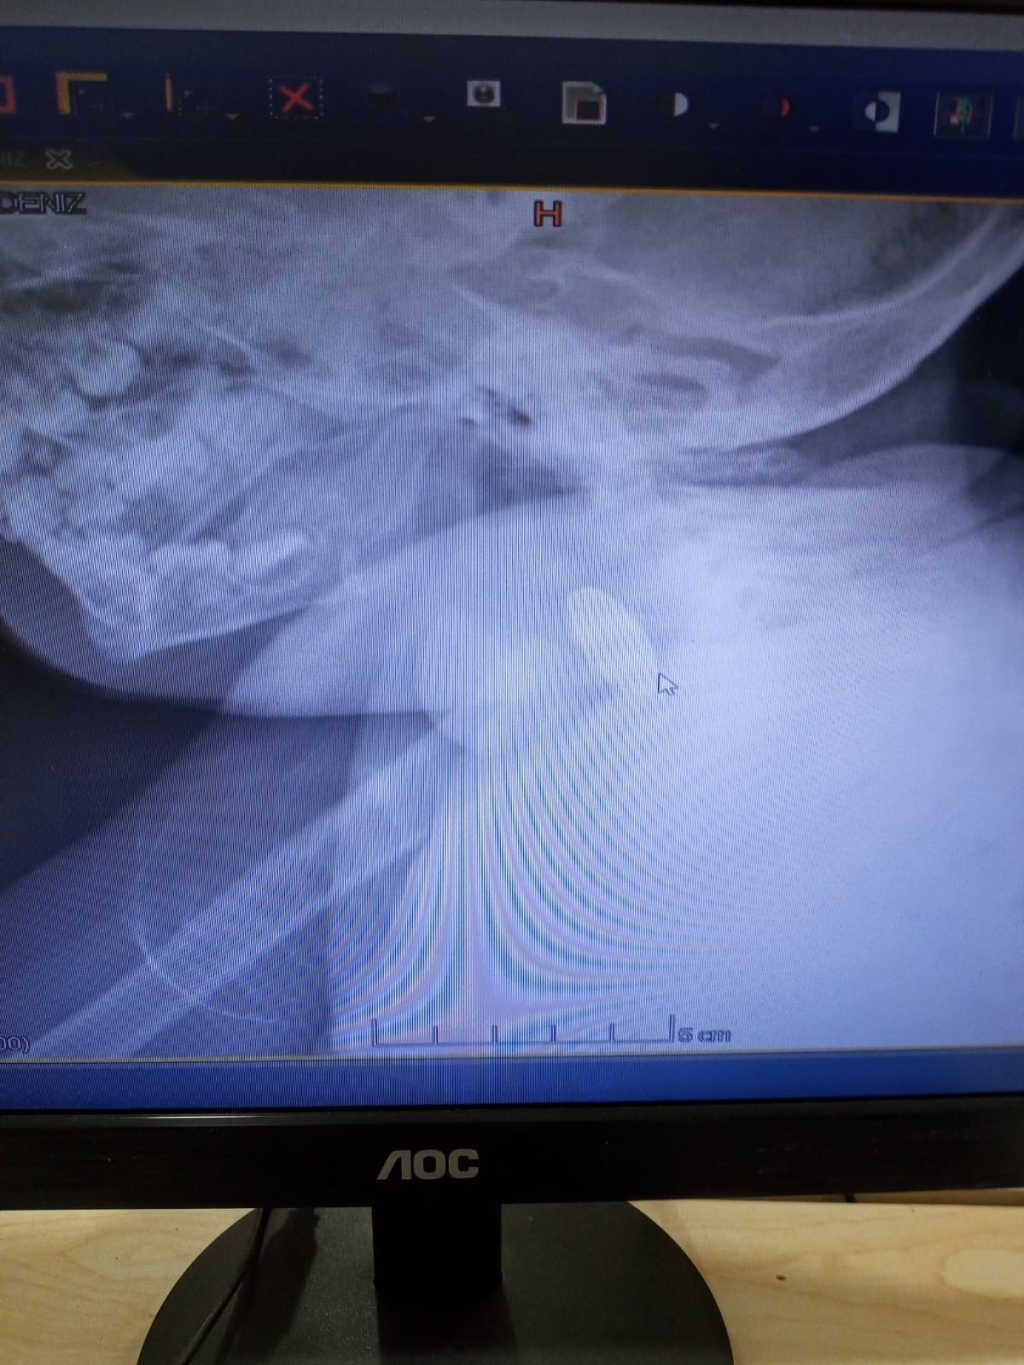

Ereğli'de evde oynarken madeni para yutan 1 yaşındaki D.D.Ç., ailesi tarafından özel hastaneye kaldırıldı. Doktorların müdahalede bulunduğu D.D.Ç.'nin çekilen röntgeninde 25 kuruşluk madeni para sindirim sistemi girişinde tespit edildi. Yapılan muayenede madeni paranın bebeğin yemek borusuna zarar vermediği anlaşıldı. Doktorların müdahalesi sırasında D.D.Ç., kusması sonucu madeni para kendiliğinden çıktı. Sağlık durumu iyi olan D.D.Ç., taburcu edildi.